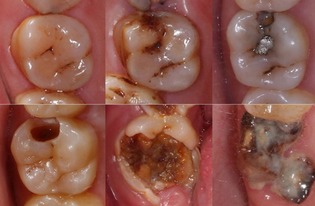

虫牙是一种常见的口腔疾病,很多人都曾经或正经历着牙齿长虫牙的痛苦。虫牙的形成是由于长期饮食、口内环境不清洁,细菌长期繁殖形成酸性环境而导致牙齿表面钙质溶解,产生菌斑、牙上石等病变,最终形成虫牙。

修复虫洞。如果虫牙已经形成,需要及时到口腔科医院进行牙齿修复,去除腐烂的牙齿组织,进行一些牙齿修复措施,例如复合树脂充填、烤瓷牙等,保留好健康的牙齿。